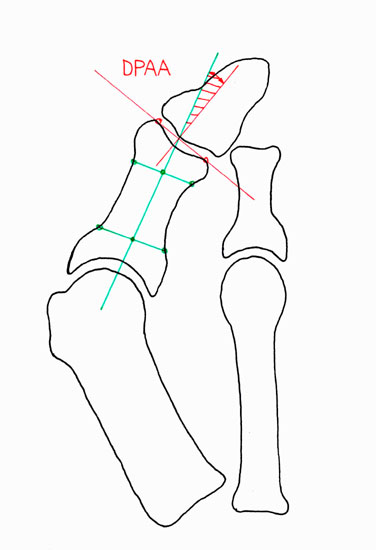

Hallux valgus Operationen gehören zu den am häufigst durchgeführten orthopädischen Eingriffen. Mit dem zunehmenden Wissen um die zugrundeliegenden pathologischen Mechanismen, kann die Anatomie der Fehlstellung präoperativ sehr genau definiert und dadurch eine präzise Planung der notwendigen Korrektur vorgenommen werden. Meistens besteht eine Fehlstellung zwischen dem ersten Metatarsalknochens und der Grundphalanx (HVA; Abb. 3a), welche häufig mit einem erhöhten Winkel zwischen Metatarsale 1 und 2 einhergeht (IMA; Abb. 3a). Seltener besteht eine Hallux valgus Fehlstellung aufgrund einer fehlgestellten distalen Gelenksfläche des Metatarsalknochens (DMAA; Abb. 3b). Die valgische Deformität der Grundphalanx mit veränderten Gelenksflächenwinkeln wird als Hallux valgus interphalangeus bezeichnet (PPAA, DPAA; Abb. 3 c-d). Die Fehlstellung wird normalerweise am Ort der Fehlstellung korrigiert. Im Rahmen der Hallux valgus Korrektur wird bei bis zu 50% der Patienten zusätzlich zur Metatarsale-Osteotomie eine Akin-Osteotomie angeschlossen 12. Eine isolierte Akin-Osteotomie ist nur in der Minderzahl der Fälle das Operationsverfahren der Wahl.

• Beurteilung des proximalen Gelenkflächenwinkels der Grundphalanx (Proximal Phalangeal Articular Angle, PPAA) sowie des distalen Gelenkflächenwinkels der Grundphalanx (Distal Phalangeal Articular Angle, DPAA) 56 (Abb. 3c und 3d).